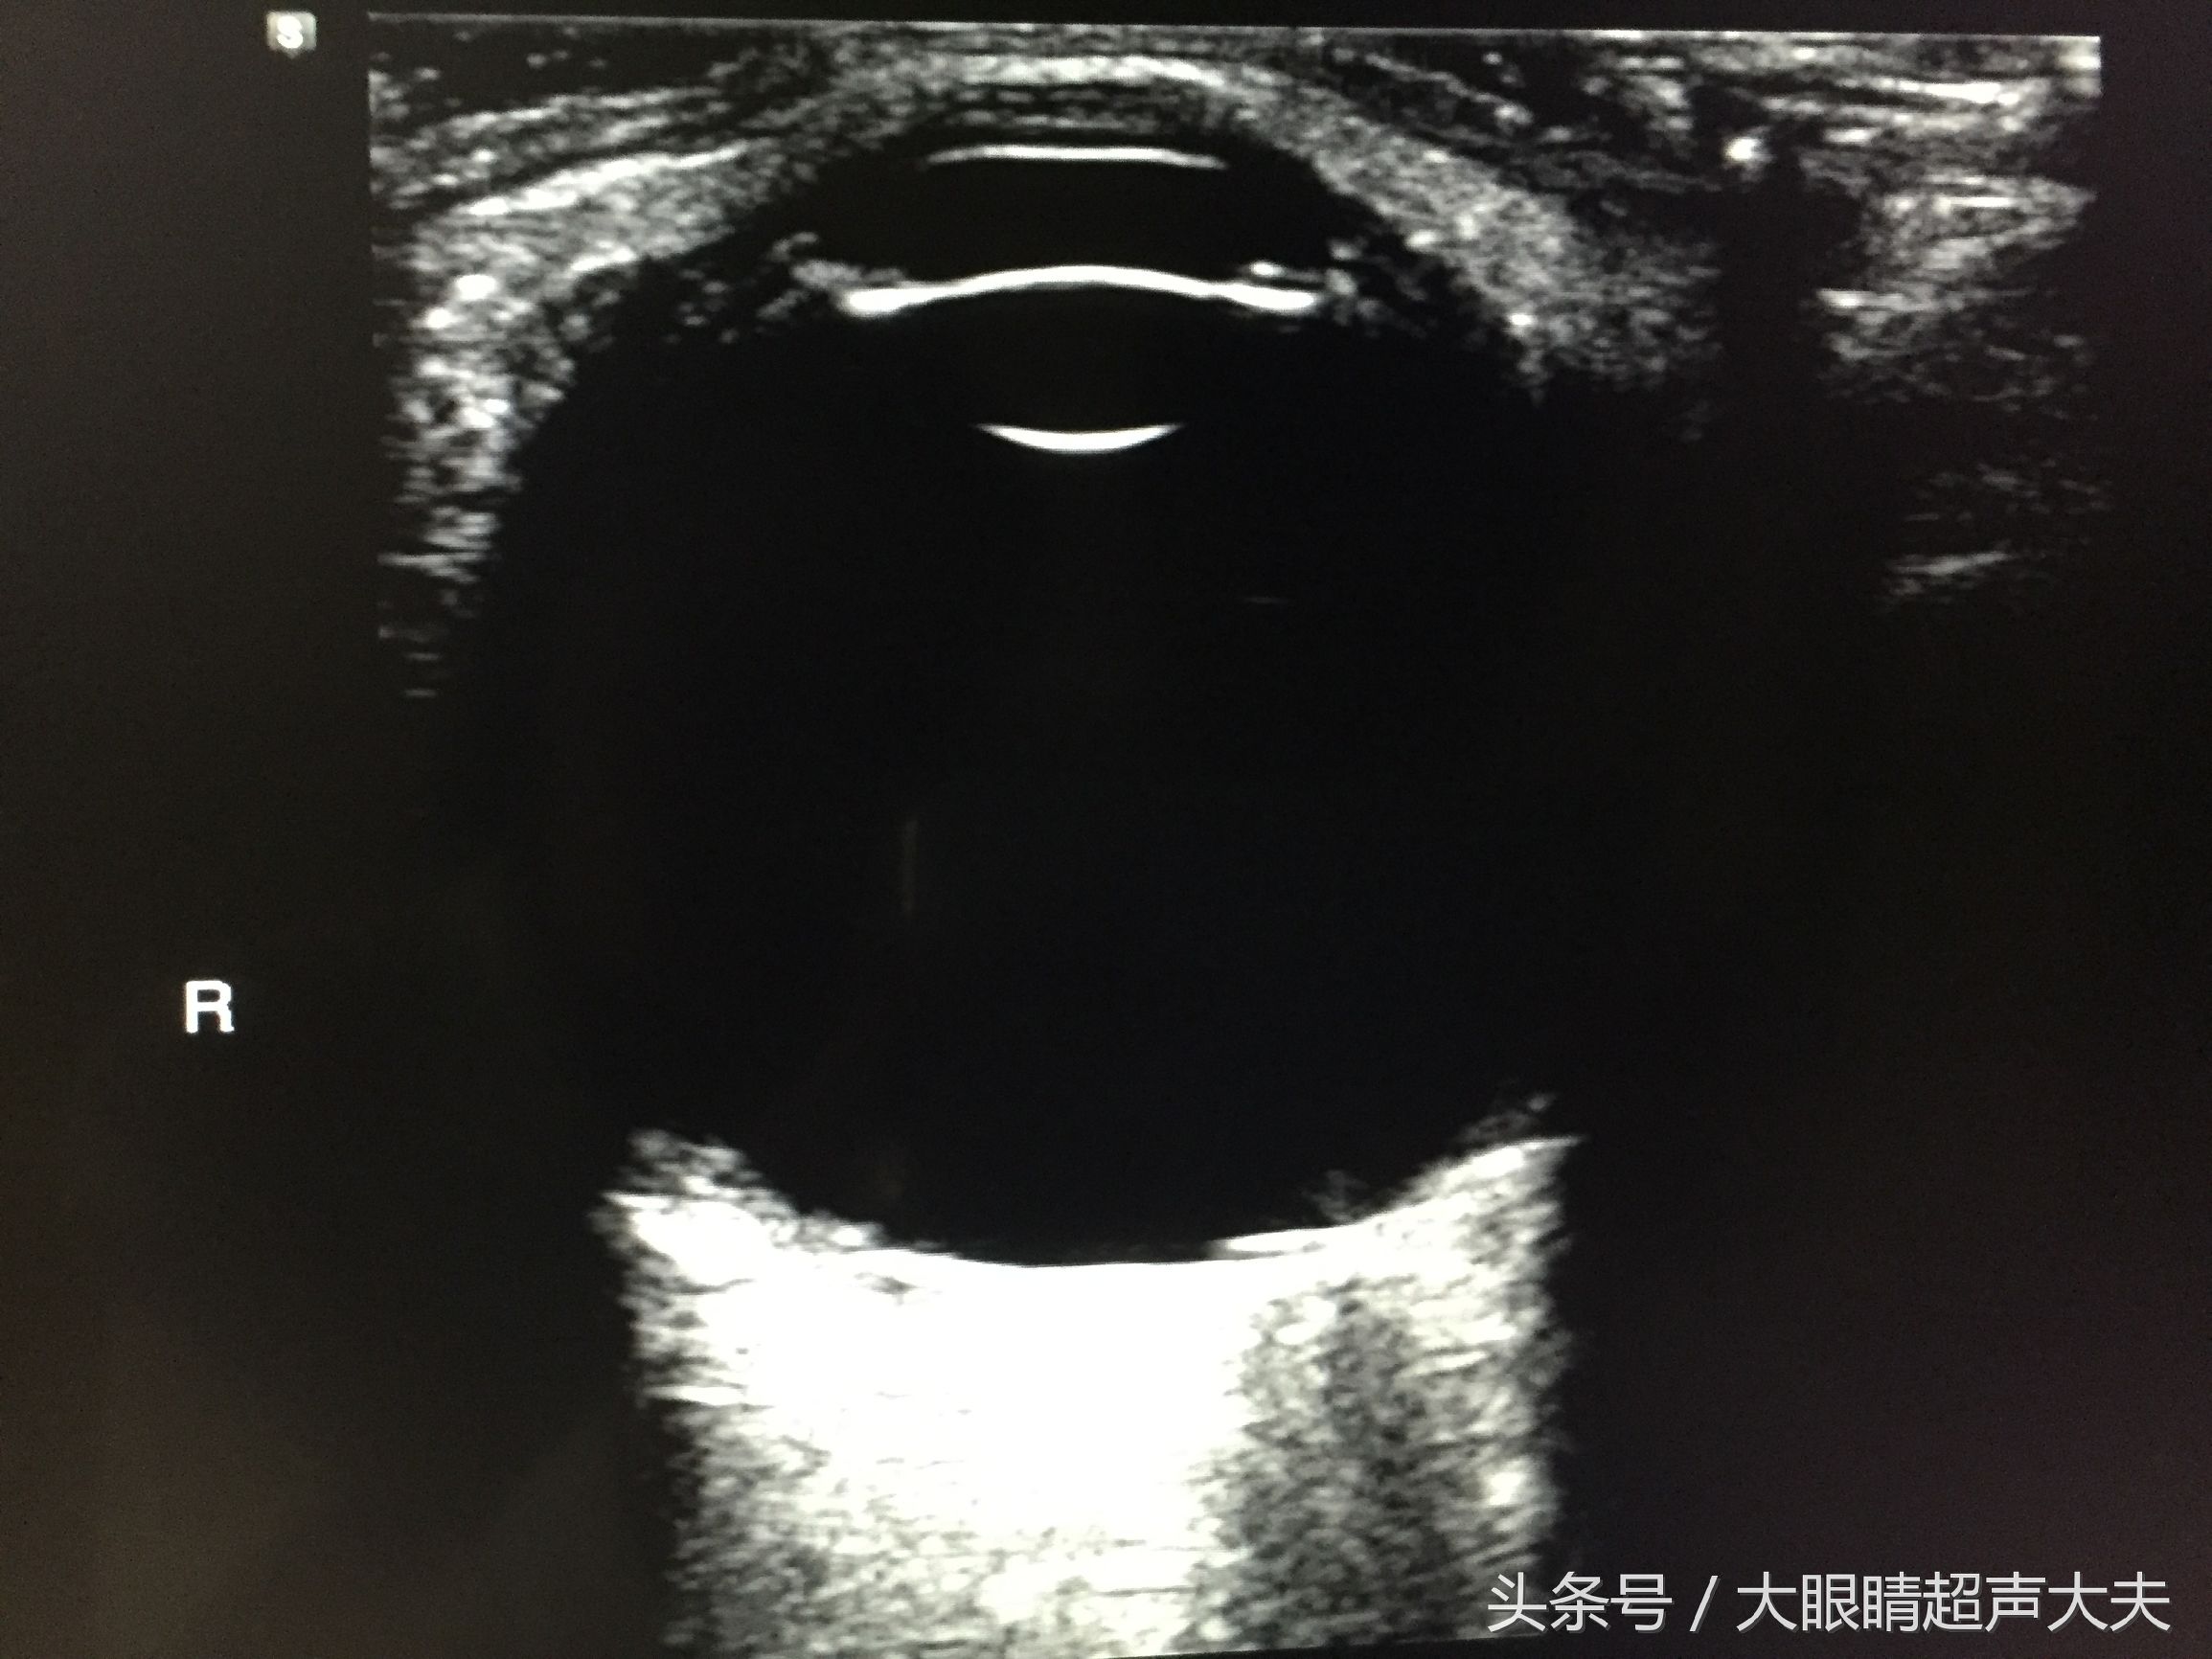

那么腹超就是医生把探头经过你的腹部去检查,看你身体内部的情况,就像图片1中我给大熊肚子上做B超一样,嘻嘻~。阴超/肛超就是将探头放进阴道/肛门里去检查盆腔脏器的情况。心超、眼超等就是专门检查心脏、眼睛等部位的超声检查(上图就是心脏彩超)。下图是眼超: